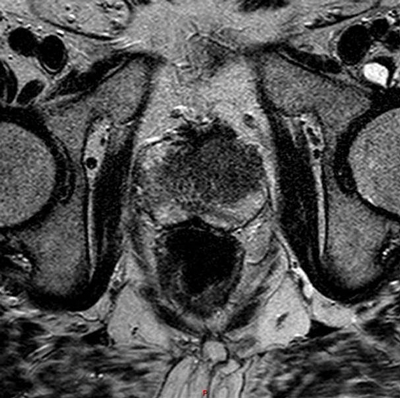

T4 disease is spread of tumour into adjacent tissues other than seminal vesicles, such as bladder, rectum or pelvic side-wall. Invasion is demonstrated by loss of the fat plane between the tumour and the structure, or in cases of more aggressive disease, visualisation of tumour within that structure (Figure 7) [3]. The sagittal T2W sequence is particularly useful at identifying bladder and rectal invasion [4].

Figure 7: Axial T2 showing extensive prostate tumour invading the bladder and bilateral iliac lymph nodes.

Large FOV axial T1W images are most useful for identifying local adenopathy. Criteria similar to those used in CT staging are often applied to MR to define clinically significant nodal involvement. Enlarged, spherical lymph nodes measuring at least 1cm in short axis dimension with loss of normal internal architecture are considered significant (Figure 7). Large FOV multiplanar T2W images of the abdomen and pelvis may be acquired to look for distant nodal disease or distant organ involvement. This is used in conjunction with CT, particularly in stage III or IV disease and when considering pre-treatment lymph node sampling [7]. T1 images should be evaluated to assess for bone metastases and will be seen as low signal intensity compared with the normal high signal marrow fat.